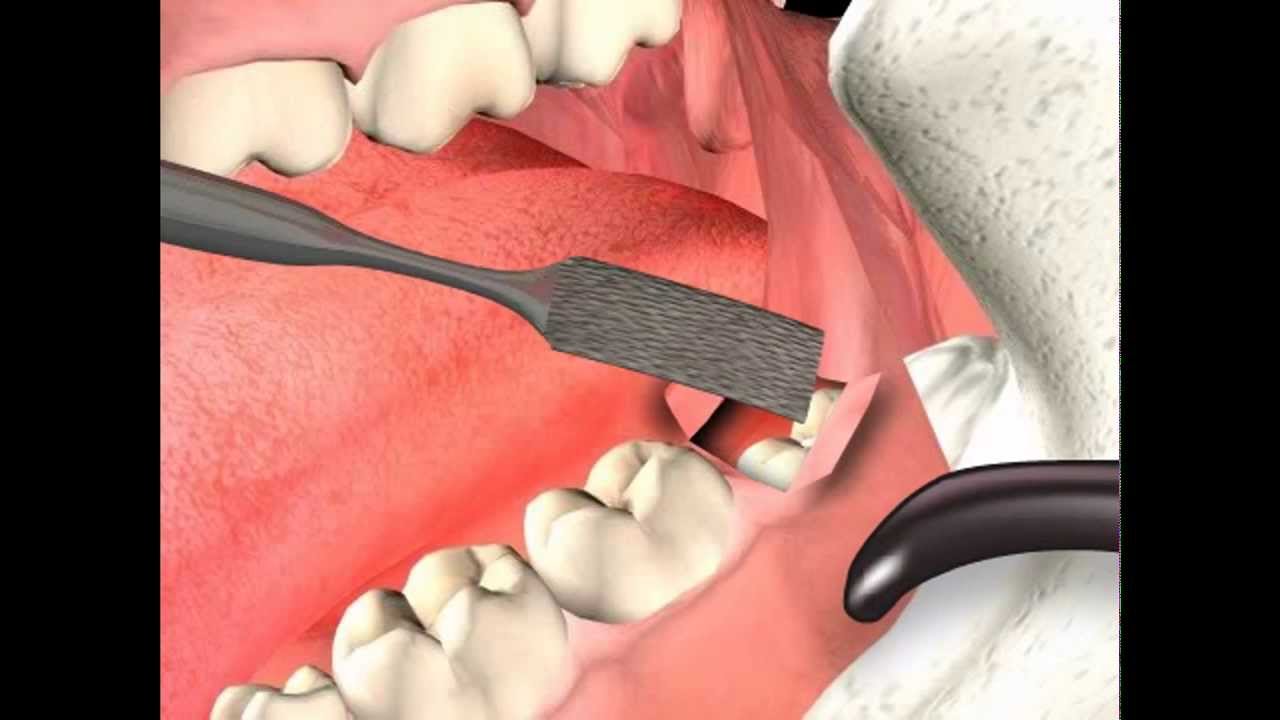

Visualizza Estrazione dente del giudizio incluso con chirurgia sonica - Dr. Fabio Cozzolino di tendenza

Visualizza Rimozione dente del giudizio

Togliere i denti del giudizio: tipologie di intervento e costi popolare